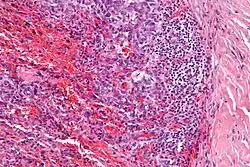

Micrograph showing an angiomatoid fibrous histiocytoma. H&E stain. |

Angiomatoid fibrous histiocytoma (AFH) is a rare soft tissue cancer that affects children and young adults.

It is characterized by cystic blood-filled spaces and composed of histiocyte-like cells. A lymphocytic cuff is common. It often simulates a vascular lesion, and was initially described as doing this.[1]